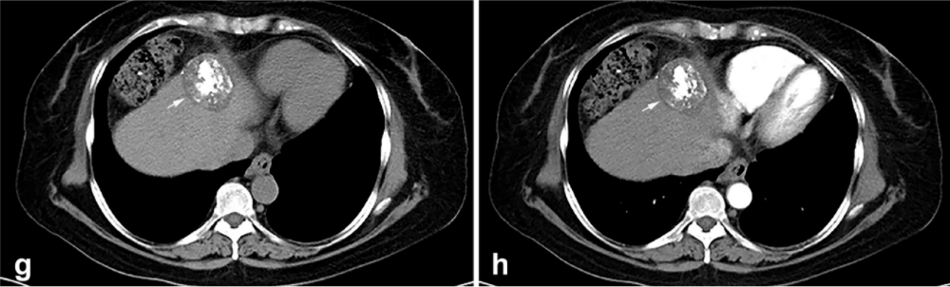

背景:由于一些原因,位于膈肌附近的腫瘤的熱消融在技術(shù)上具有挑戰(zhàn)性。首先,術(shù)中計(jì)算機(jī)掃描和超聲檢查無(wú)法清晰顯示射頻消融/微波消融切緣。第二,消融過(guò)程中不利的針?lè)植己瓦^(guò)熱可能導(dǎo)致肝包膜破裂,并對(duì)膈、肺和心臟造成嚴(yán)重?fù)p傷。第三,即使使用人工腹水,仍有9~22%的患者因肝周粘連或腫瘤位置靠近肝表面而導(dǎo)致膈肌熱損傷。冷凍消融可能是毗鄰膈肌的HCC的一種有前途的治療方法,因?yàn)樵谙谶^(guò)程中使用CT和US可以很好地顯示腫瘤邊緣。盡管一些研究評(píng)估了在高危區(qū)域使用冷凍消融治療HCC,但很少有研究針對(duì)膈肌臨近區(qū)域。

背景:肝癌是中國(guó)最常見(jiàn)的惡性腫瘤之一,發(fā)病率和死亡率都很高。雖然手術(shù)切除是最好的治療方法,但大多數(shù)患者處于晚期或直到住院才有手術(shù)指征。對(duì)于單個(gè)腫瘤直徑小于5厘米的患者,微創(chuàng)治療與手術(shù)切除效果相當(dāng);多個(gè)病灶小于3個(gè),單個(gè)病灶最大直徑小于3cm;不侵犯血管、膽管、鄰近器官和遠(yuǎn)處轉(zhuǎn)移。雖然一些傳統(tǒng)消融技術(shù)方式可以使部分患者受益,但不適用于特殊部位肝癌(定義為毗鄰大血管、肝外臟器和重要結(jié)構(gòu)的腫瘤)的治療。冷凍消融作為一種相對(duì)較新的治療方式,具有明顯的冰球效果、療效好、激活抗腫瘤免疫、并發(fā)癥發(fā)生率低等優(yōu)點(diǎn),尤其適用于特殊部位肝癌患者的治療。我們的研究目的是探討CA治療特殊部位肝癌的安全性、可行性和有效性。

① 在我們的研究中,技術(shù)成功率為100%。動(dòng)態(tài)增強(qiáng)MR檢查隨訪1個(gè)月,66例患者首次技術(shù)有效率為65例(98.5%),MR影像學(xué)未發(fā)現(xiàn)外周臟器損傷。中位隨訪時(shí)間14個(gè)月(范圍2-28個(gè)月)。高危部位肝癌局部腫瘤進(jìn)展率曲線:6、9、15和24個(gè)月的累積局部腫瘤進(jìn)展率分別為10.2%、16.5%、20.9%和30.5%。